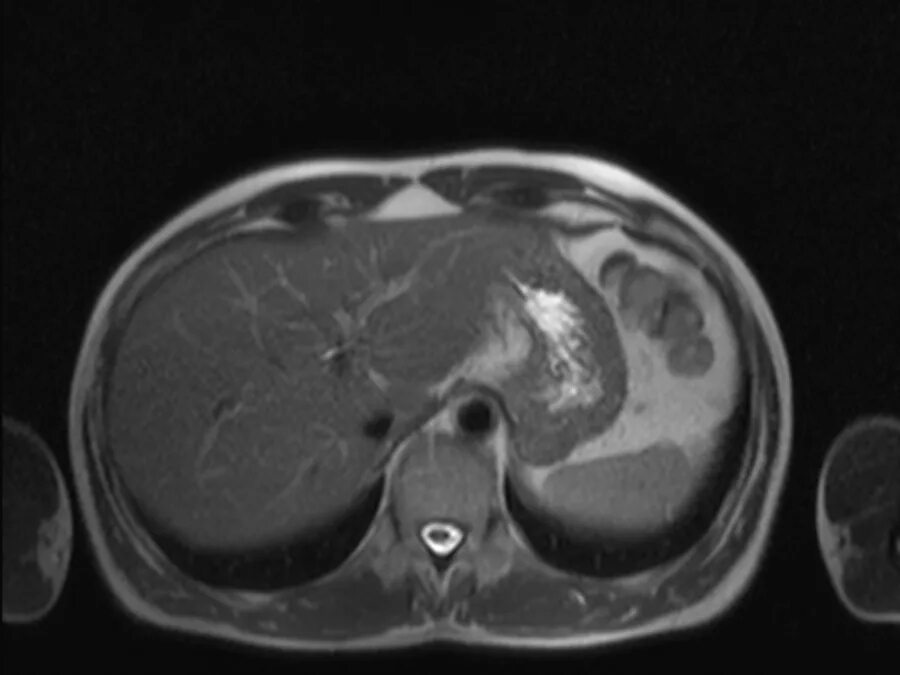

Что проверяет мрт брюшной полости